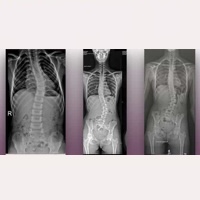

脊柱側彎

原發性脊柱側彎